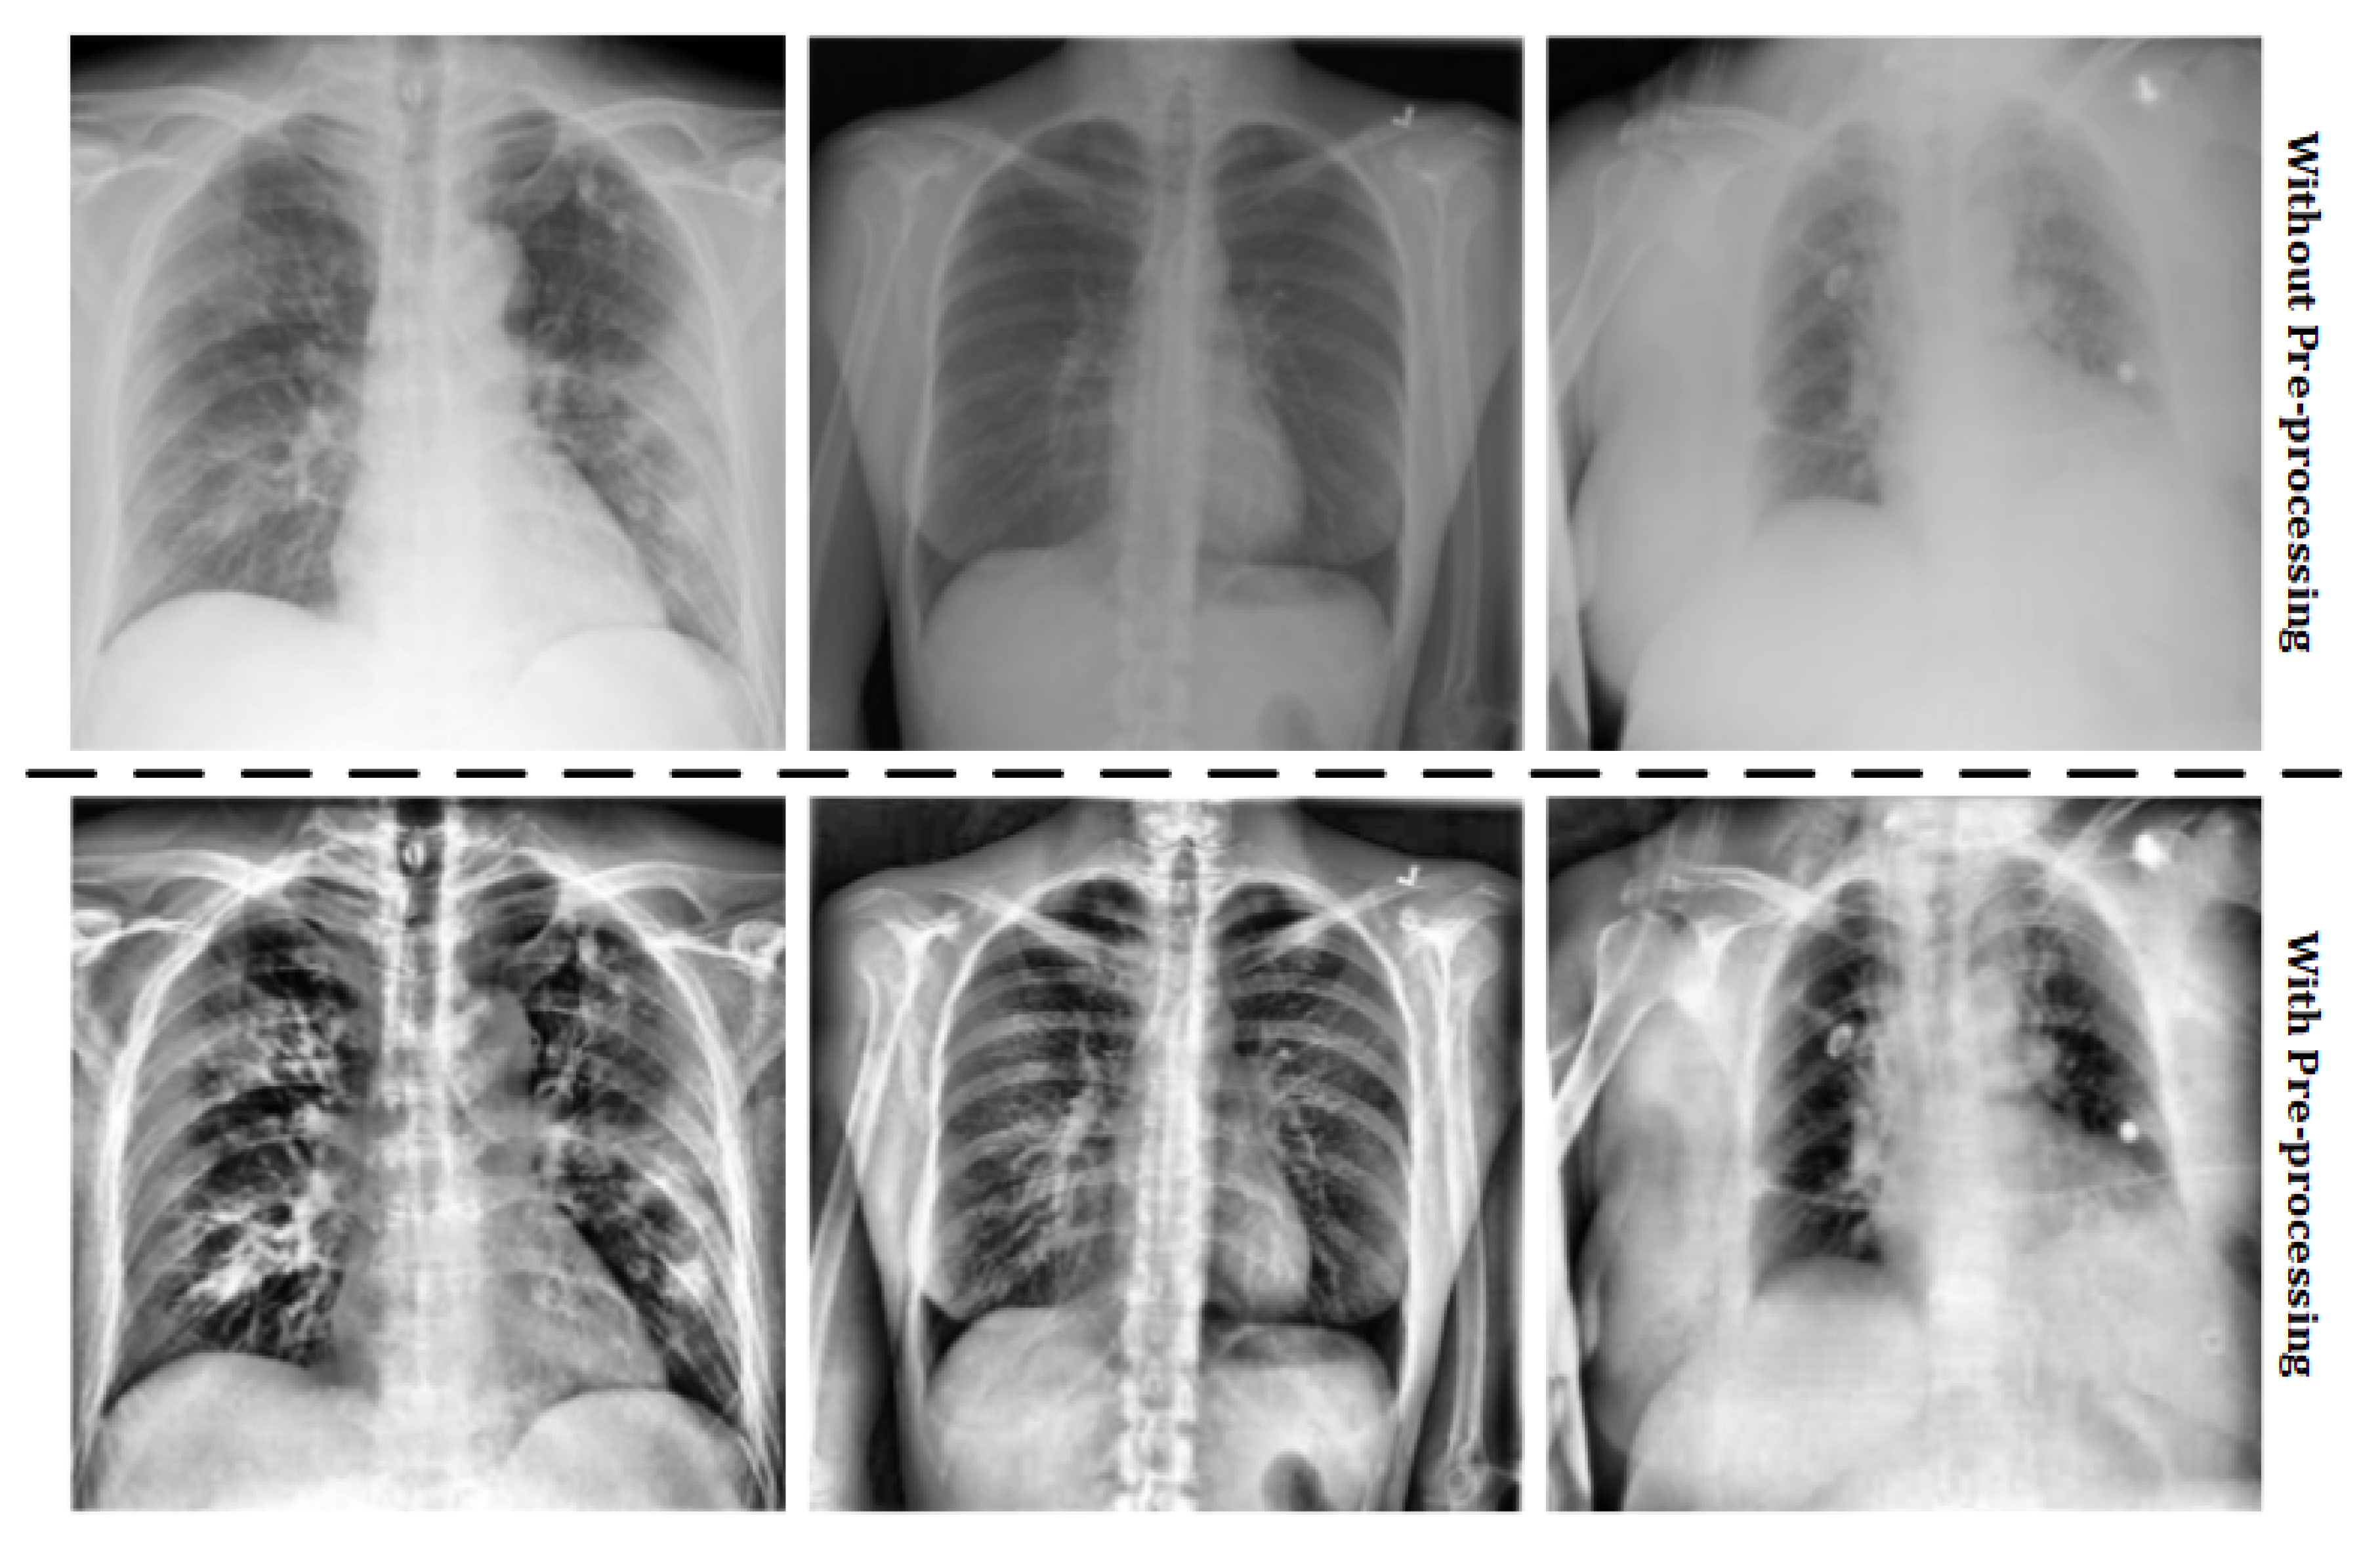

Applied Sciences | Free Full-Text | Deep Learning System for COVID-19  Diagnosis Aid Using X-ray Pulmonary Images | HTML Applied Sciences | Free Full-Text | Deep Learning System for COVID-19 Diagnosis Aid Using X-ray Pulmonary Images | HTML